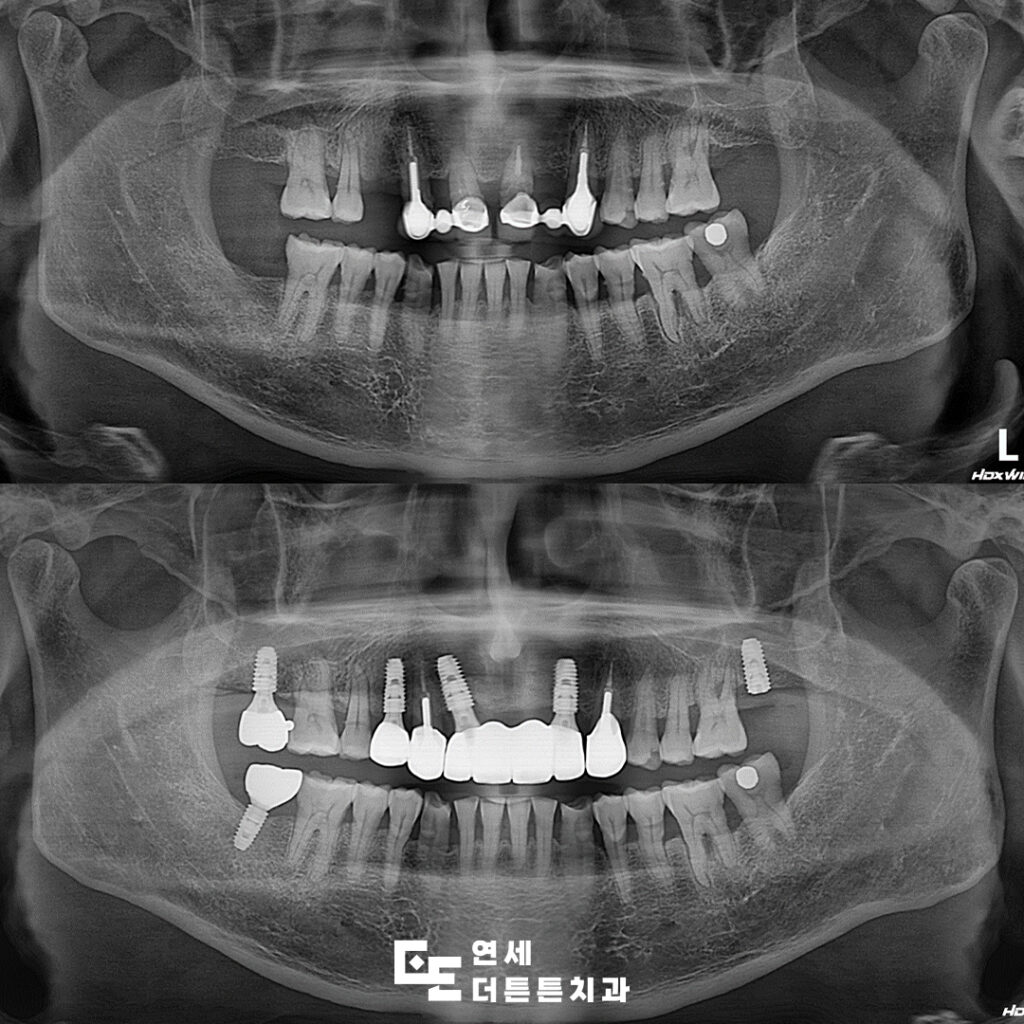

먼저 식립한 임플란트는

최종 보철물을 마무리하고

왼쪽 위 어금니는 기존 잇몸뼈와

충분히 융합될 수 있도록 기간을 기다려준 뒤

최종 보철물을 진행할 예정입니다.

임플란트는 치료 과정과 그 결과가

개인마다 달라지기도 하는데

대부분은 수술 부위의 뼈 상태에 따라

달라지게 되어 단단하고 충분한 두께의 뼈에

임플란트가 식립되면 2~3개월 후 완료될 수 있다고 봅니다.

이는 수술 이후 턱뼈가 임플란트를

단단하게 잡아주는 골유착이 일어나는 시간을

보통 3개월 정도로 보기 때문인데요.

하지만 뼈가 부족하여 뼈이식을 많이 했다면

기간이 길어질 수 있고, 시술 부위의 뼈가 부족하거나

얇은 경우 시술과 함께 진행되기도 하며

경우에 따라 뼈이식을 먼저 진행하고

2~3개월 후 시술을 하기도 합니다.